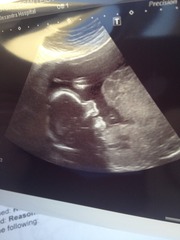

FeatheredTail · 23/12/2015 12:54

All healthy - apart from the baby was being lazy and wouldn't move to allow for it's spine to be checked, so I have to go back for spinebifada check. Didn't find out tr sex, but sonographer was a knob - I asked of she'd have a look round the willy/fanny area and she said she would and would tell us what she saw. I asked if she would just have a look so we could see and guess - and she said "why would I do that?" And that was it! Weirdo!

FeatheredTail · 23/12/2015 12:56

Anyone want to take a guess?! Body shot and smiling face shot!

Beautiful pics feathered! Lovely and clear!

Sounds like your sonographer was a bit odd, but I'm glad everything's looking good.

lovely scan pic feathered :) scanner sounds like a dick though!